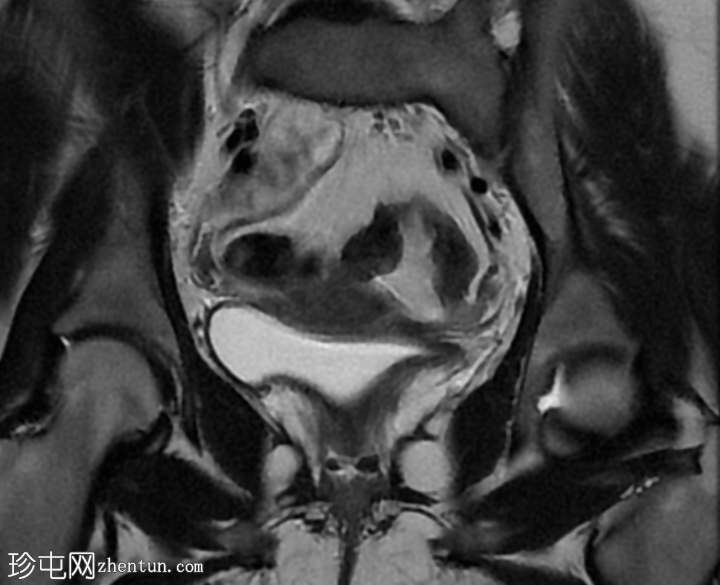

矢状位

T2加权像

子宫体积较小,最大横径、前后径和头尾径均为3.0 x 3.0 x 2.7 cm。子宫体与宫颈的比例为1.3:1。子宫无明显分区结构。

双侧卵巢发育不良,无卵泡活动。